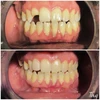

Crooked Teeth

Zirconium Applications

Porcelain Applications

Laminate Veneer